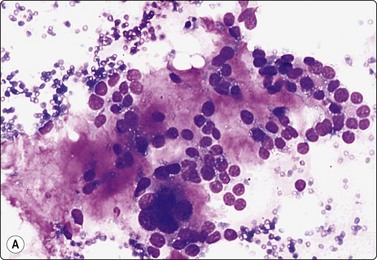

image image image

Fig. 7.19 Fat necrosis

(A) Postoperative fat necrosis. Necrotic tissue, debris and macrophages; fragment of adipose tissue upper right (MGG IP); (B) Fragments consisting of altered adipocytes, macrophages and fat droplets (MGG, IP); (C) Several multinucleated histiocytes with foamy cytoplasm (MGG, HP).

Postoperative changes in response to prior surgical excision or biopsy give similar findings. Fat necrosis is always in the differential diagnosis of nodules in scars or chest wall after surgery, particularly mastectomy. Vigorous or repeated palpation of breast tissue or previous aspiration of the site can result in the same changes. The aspirate is usually scanty, sometimes of oily fluid, and consists mainly of fat with some foamy macrophages or altered, vacuolated adipocytes and multinucleated histiocytic giant cells. The untidy background of granular debris represents the actual necrosis and is the most specific diagnostic feature (Fig. 7.19A,B).